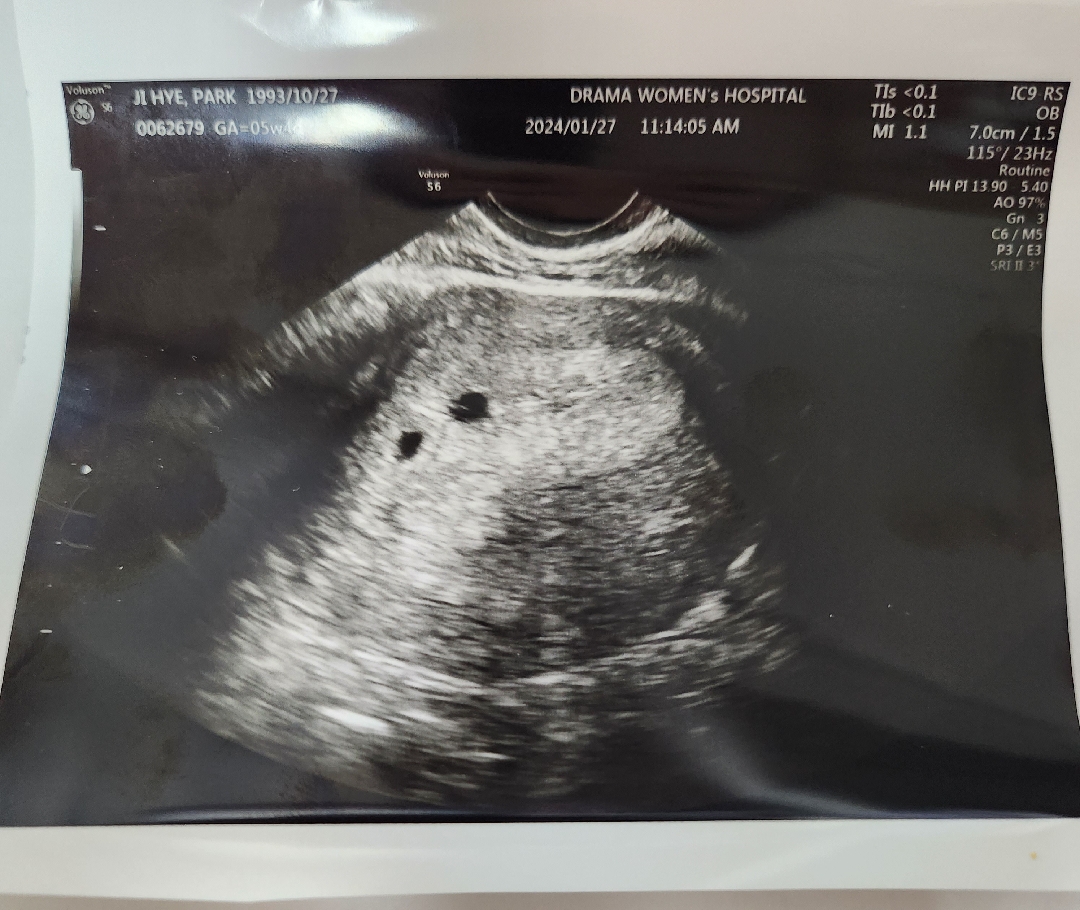

초음파 한번만 봐주시겠어요? ㅠㅠ아기집이 두개 보인다고 해서요!

오늘 아침에 파이널 체크 임테기 1번선 연한줄 나오고 오전에 드뎌 아기집 보러 갔다 왔습니다!! 아기집 보는데 의사쌤께서 아기집 같은게 두개 보인다고 말씀 해주셔서 쌍둥이일수도 있다고! 2주후에 확실하게 보이면 얘기해주신다고 하더라구요! 초음파 고수님들 한번만 봐주시겠어요? ㅠㅠ

앗 근데 난황보이기 전에는 또몰라서~ 담주에 한번 더 가보셔야 정확할거같아요♡ 축하드려요~~

아 맞아요 ㅜㅜ 난황이 보여야 확정이라고 하셔서! 어쨋든 쌍둥이도 너무 반갑네요 ㅎㅎ 축하해주셔서 감사합니다😊😊

쌍둥이 맞습니다 ^^